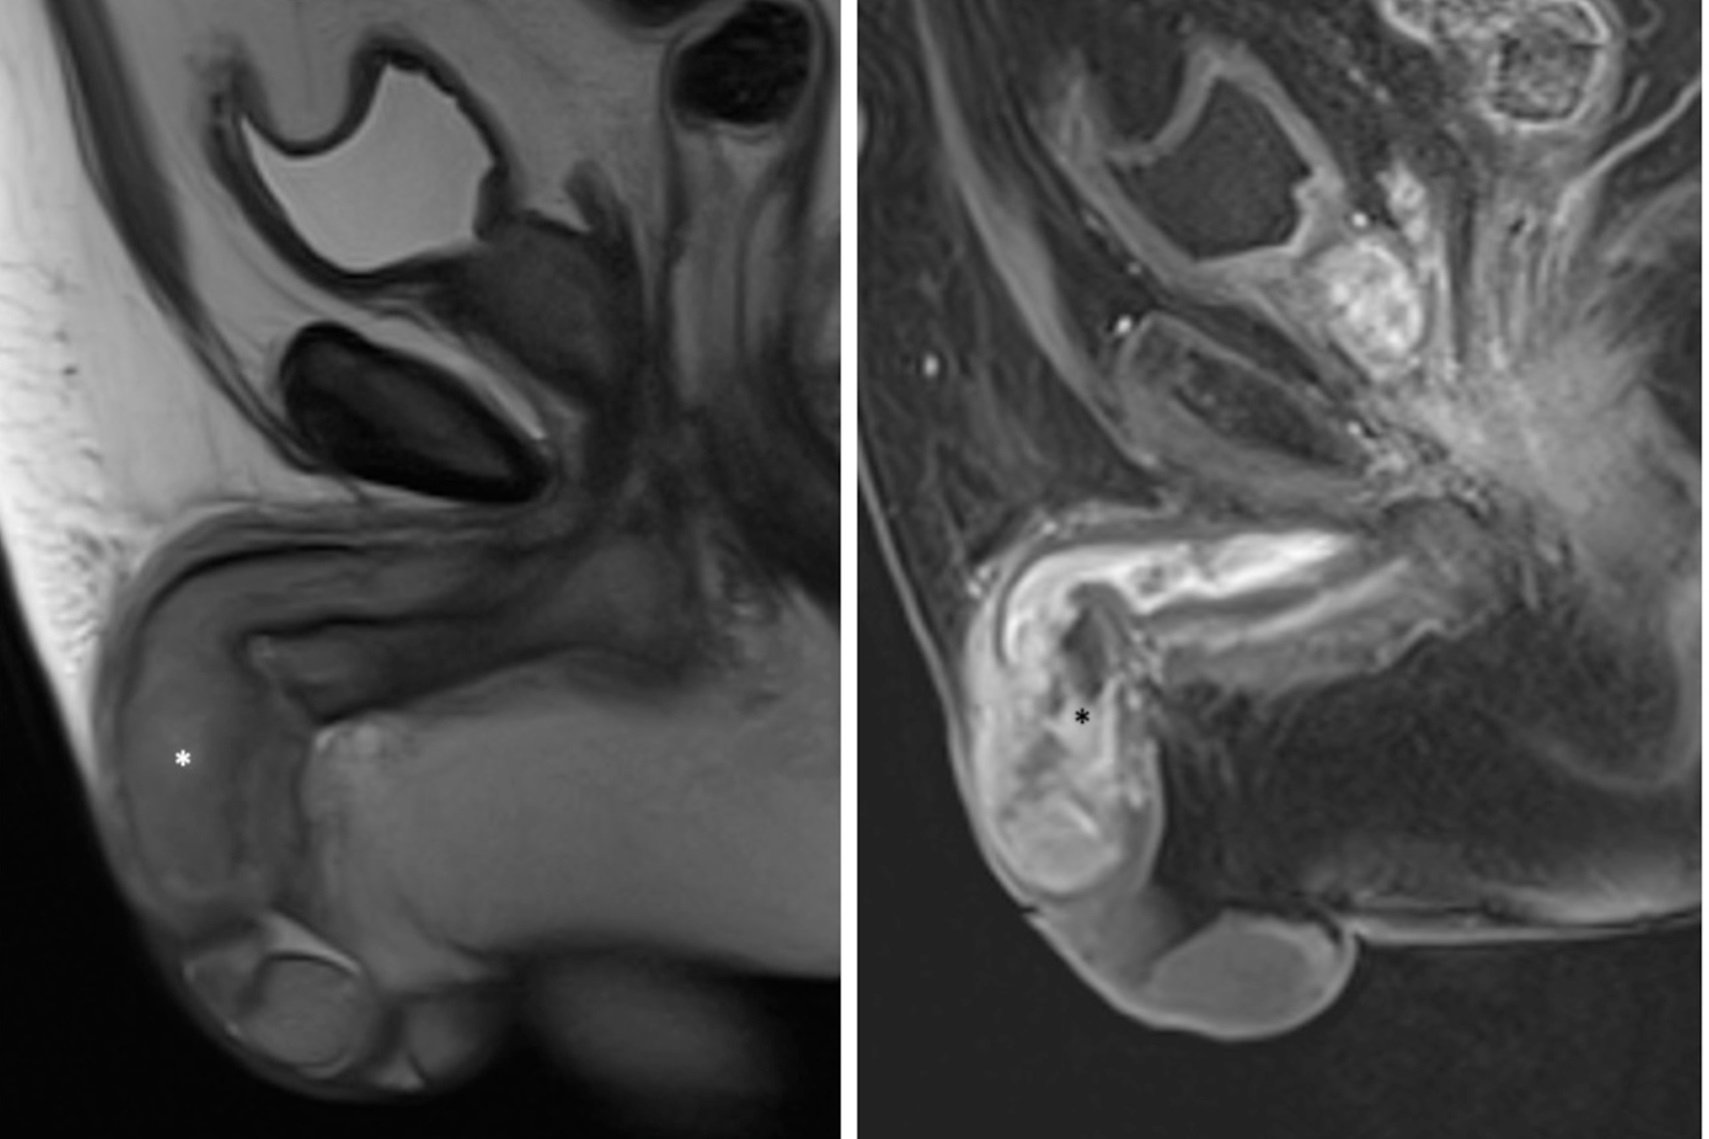

Câncer de pênis: higiene errada pode levar à amputação do órgão Ouvir 19 de novembro de 2025 Apesar de raro, o câncer de pênis foi responsável por mais de 6 mil amputações nos últimos 10 anos no Brasil. De acordo com o Ministério da Saúde, o país registrou mais de 21 mil casos da doença entre 2012 e 2022 e mais de 4 mil mortes entre 2011 e 2021. É possível prevenir o tumor de forma simples, com água e sabão. Mas, além da higiene inadequada, a doença também está relacionada à infecção pelo HPV e à não remoção do prepúcio quando ele não pode ser completamente puxado para trás para expor a glande a fim de higienizá-la. Leia também Saúde Caso raro: homem com câncer tem pênis amputado para conter metástases Saúde Estudo brasileiro traz avanço inédito no tratamento de câncer de pênis Saúde Câncer de pênis: conheça os principais sinais e como se prevenir Saúde “Teria amputado para viver mais”, diz homem que teve câncer de pênis “O Brasil está na relação dos países com maior incidência de câncer de pênis. E uma das razões para isso é a falta de informação da população da sua existência, do diagnóstico tardio e de que dá para evitar a grande maioria dos casos com água, sabão e vacinação”, destaca o presidente da Sociedade Brasileira de Urologia (SBU), Luiz Otavio Torres. O câncer de pênis não é comum e pode ser prevenido de maneira simples, com água, sabão e vacinação Fatores de risco e sintomas do câncer de pênis O câncer de pênis é mais incidente em homens a partir dos 50 anos, mas também pode atingir os mais jovens. Entre os fatores de risco estão: Baixas condições socioeconômicas; Má higiene íntima; Fimose (estreitamento da pele que recobre o pênis); Infecção pelo vírus HPV (papilomavírus humano); Tabagismo. Saiba quais são os sintomas na reportagem do Saúde em Dia, parceiro do Metrópoles. Siga a editoria de Saúde e Ciência no Instagram e fique por dentro de tudo sobre o assunto! Notícias